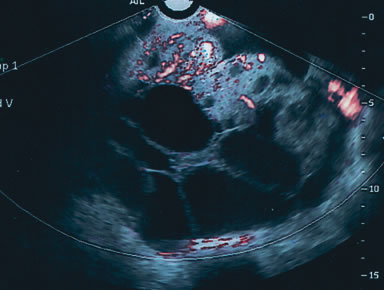

Fig. 4. A complex 12 × 10-cm mass in a premenopausal woman contained multiple septations with solid elements that had marked vascular flow. The mass was correctly identified as malignant (Stage III papillary adenocarcinoma).